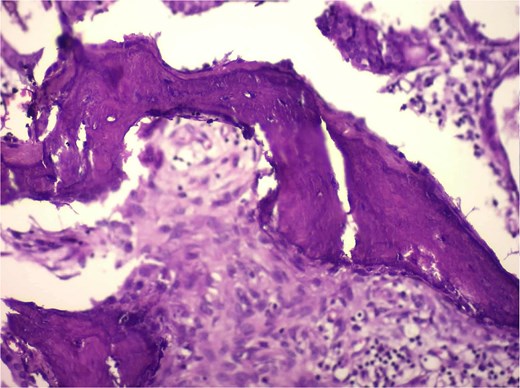

Histological analysis showed mucosal invaginations forming Rokitansky–Aschoff sinus–like diverticula surrounded by hypertrophic smooth muscle bundles, consistent with adenomyosis. The stroma exhibited lymphoplasmacytic infiltrates, hypertrophied nerve fibers, and vascular dystrophy. In deeper sections, areas of vascularized granulation tissue contained trabecular bone formation, confirming osseous metaplasia. No dysplasia or neoplastic proliferation was identified (Figs 2–4).

High-magnification histology showing osseous metaplasia (H&E) high-power photomicrograph demonstrating irregular trabeculae of eosinophilic osteoid matrix with embedded osteocyte-like cells, consistent with mature bone formation within adenomyosis. No atypia or malignancy is present.